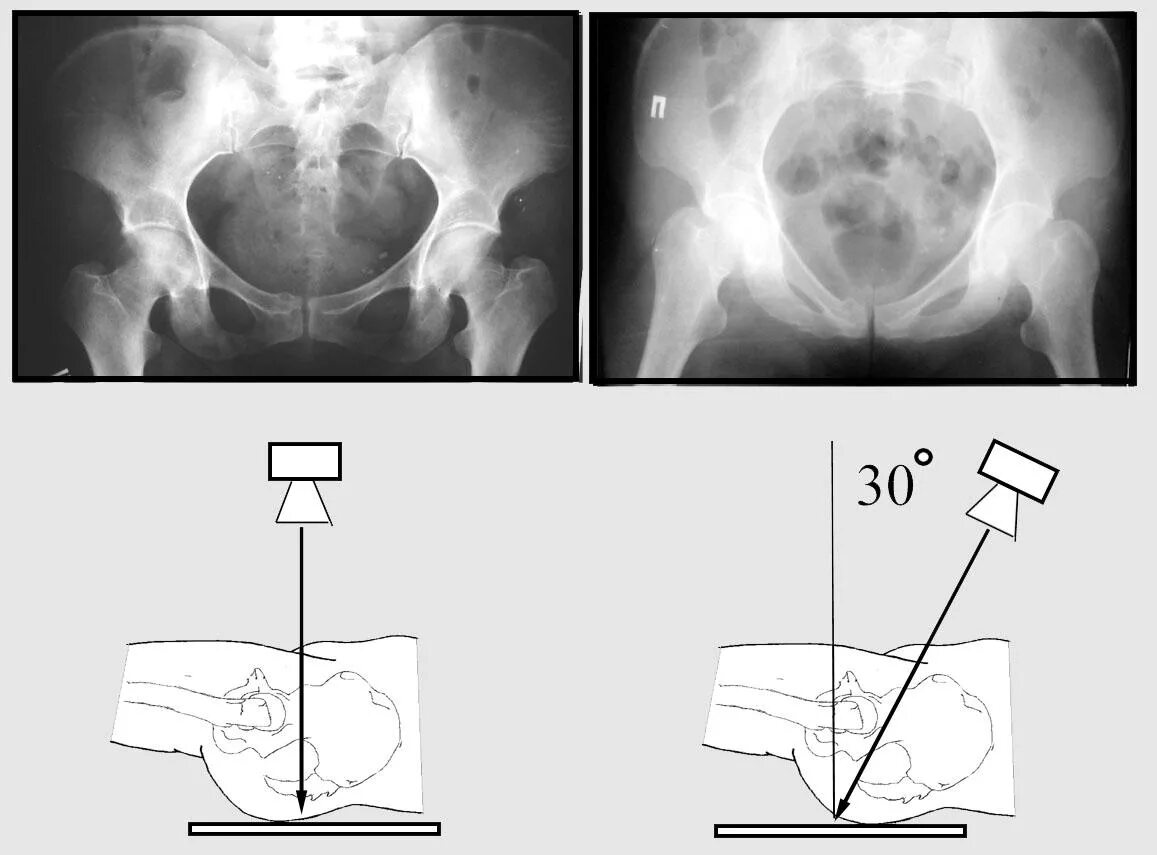

Рентген тазобедренный в двух проекциях